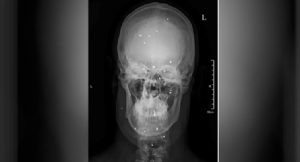

shahin-balles-de-plombs-iran-csdhi

Une arme aveuglante (3) : Shahin, touché par 90 plombs, au moins

CSDHI – Comme l’a rapporté IranWire, des centaines d’Iraniens ont subi de graves blessures aux yeux après avoir été touchés par des plombs, des bombes lacrymogènes, des balles de paintball ou d’autres projectiles utilisés par les forces de sécurité dans le cadre d’une répression sanglante de manifestations essentiellement pacifiques. Selon les médecins, à ce jour, […]